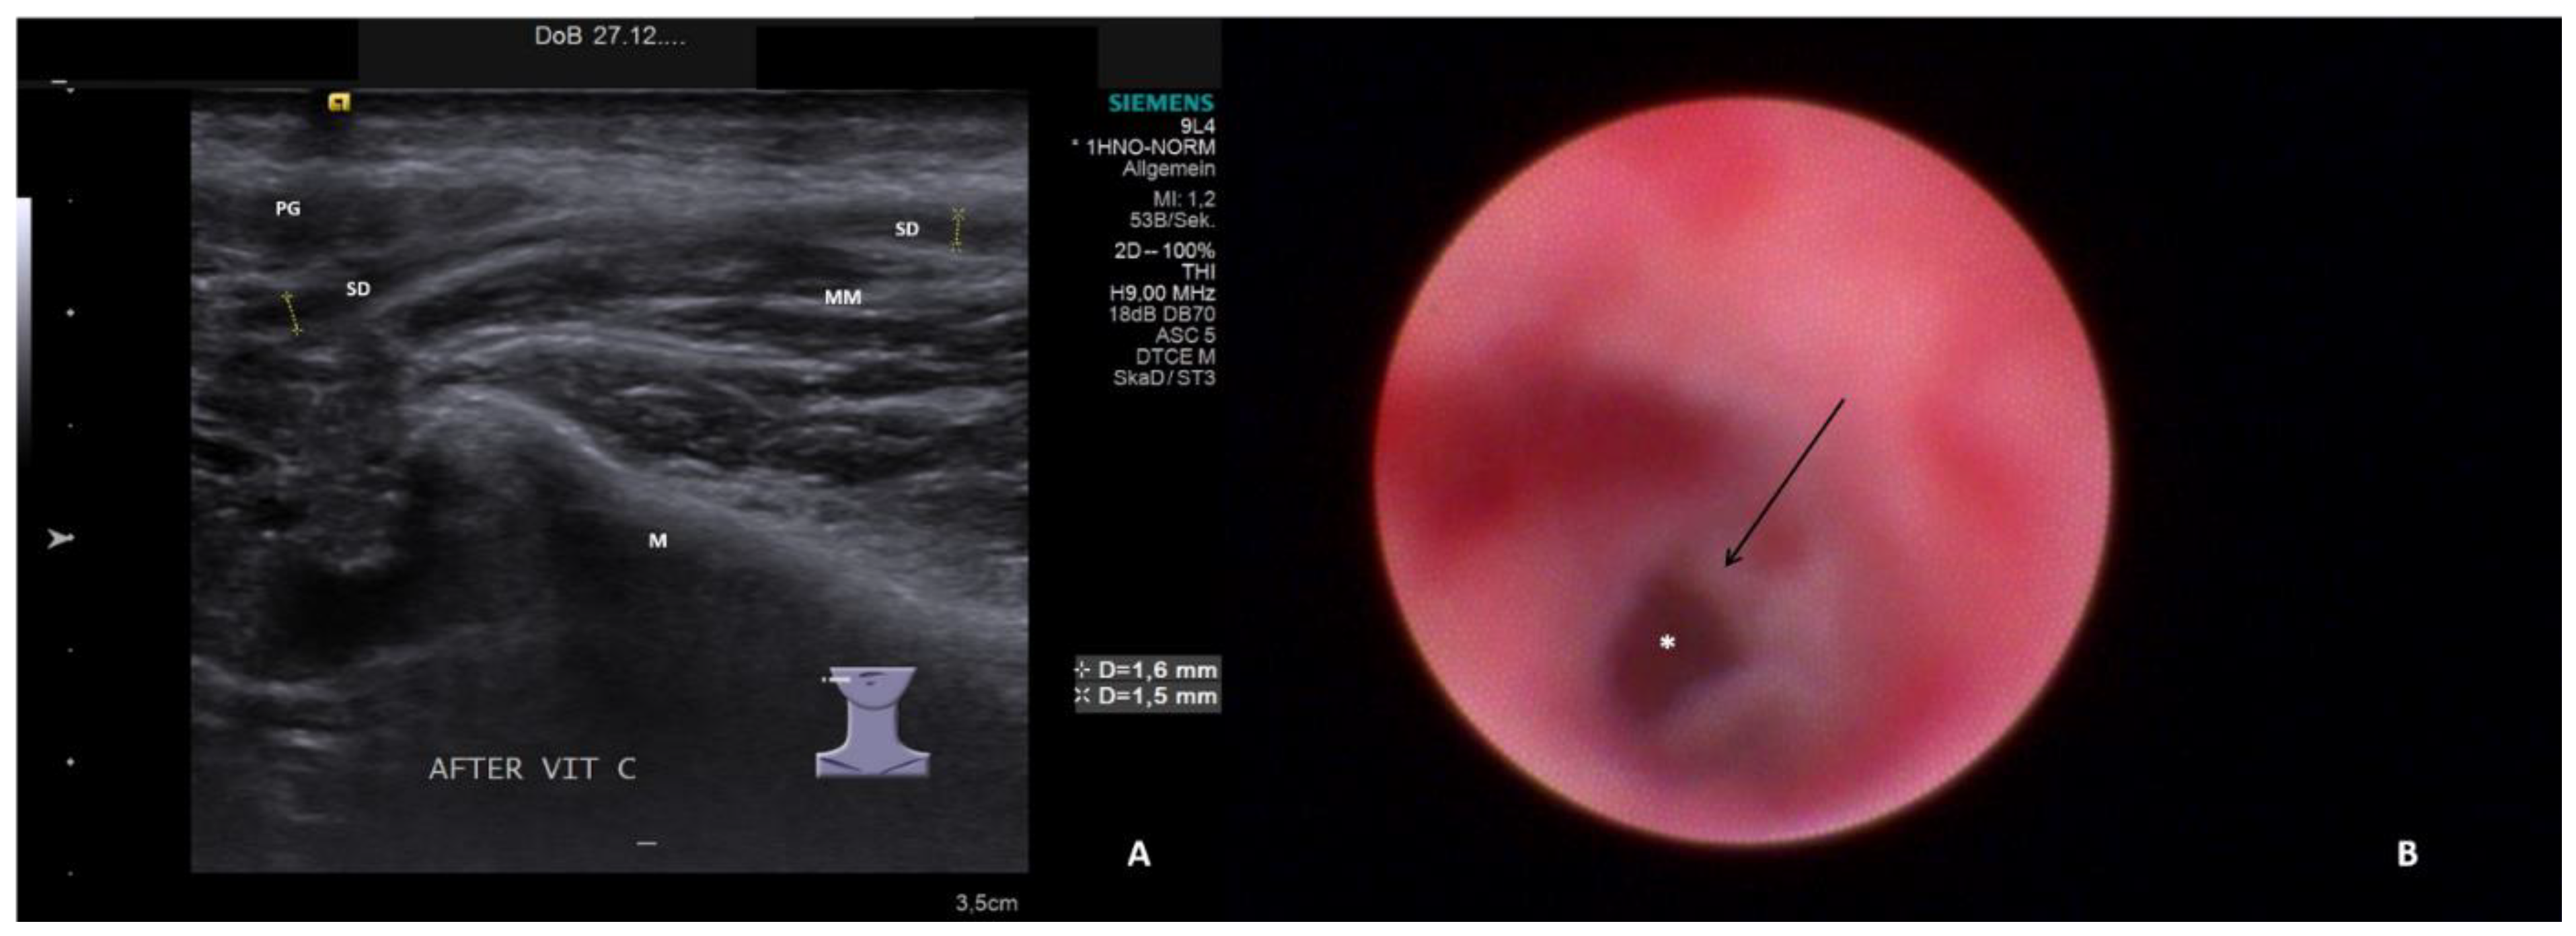

- Sialodochitis with a tendency toward duct narrowing (SD + Sten: SD and thickness of the duct wall with a tendency toward luminal narrowing; Figure 2B; Supplementary Video S2)